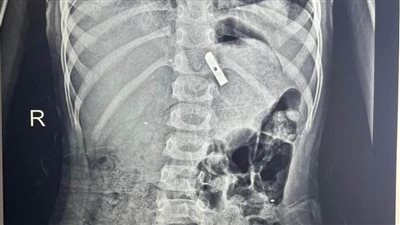

إنقاذ حياة طفل ابتلع مسمار دباسة بمستشفى الأطفال التخصصي في بنها

الأحد 23/نوفمبر/2025 - 10:38 م